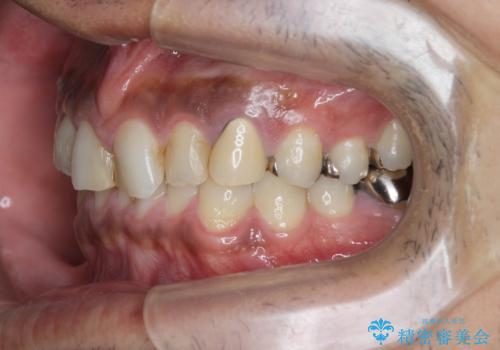

- 治療計画

- 長年虫歯の治療を受け続けたことで銀歯・コンポジットレジン修復だらけになってしまい、今後の見た目や歯を大切にするためにセラミック治療矯正治療を希望され来院されました。

マイクロスコープを用いた精密根管治療やセラミック治療、マウスピース矯正治療を一つの医院で行うことのできる当法人ならではの総合歯科治療を実践していきます。